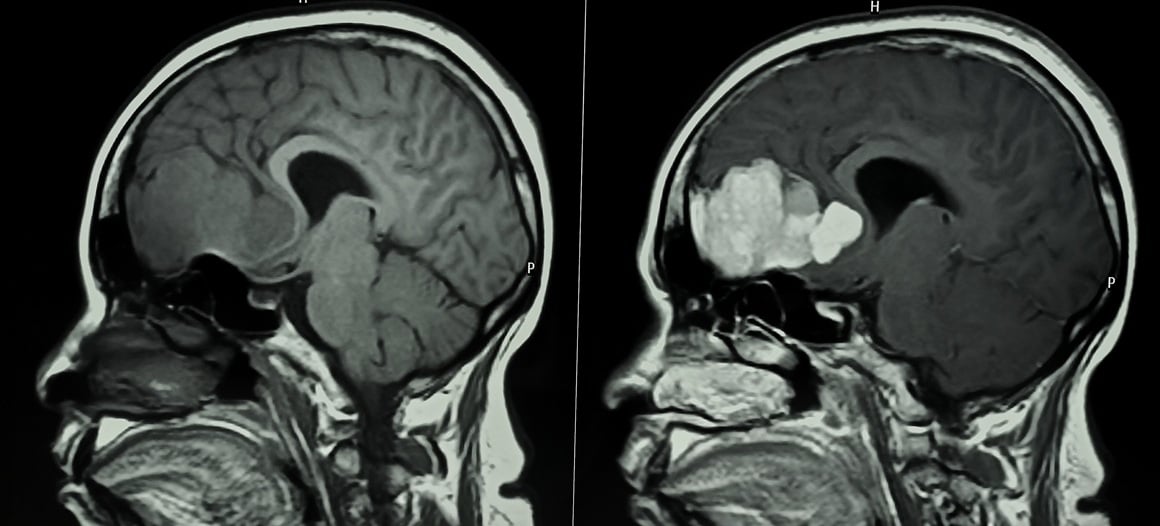

Magnetska rezonancija često se smatra rutinskom i sigurnom pretragom, no za neke pacijente ona može imati neugodne posljedice. Posebno kada uključuje kontrastno sredstvo, MR snimanje može potaknuti nuspojave koje značajno utječu na kvalitetu života.

Reem Khatib, koja živi s multiplom sklerozom, svakih šest mjeseci prolazi magnetsku rezonanciju kako bi pratila tijek svoje bolesti.

Kako je ispričala za WebMD, kontrastno sredstvo daje se putem infuzije kako bi se određene strukture u tijelu jasnije prikazale na snimkama.